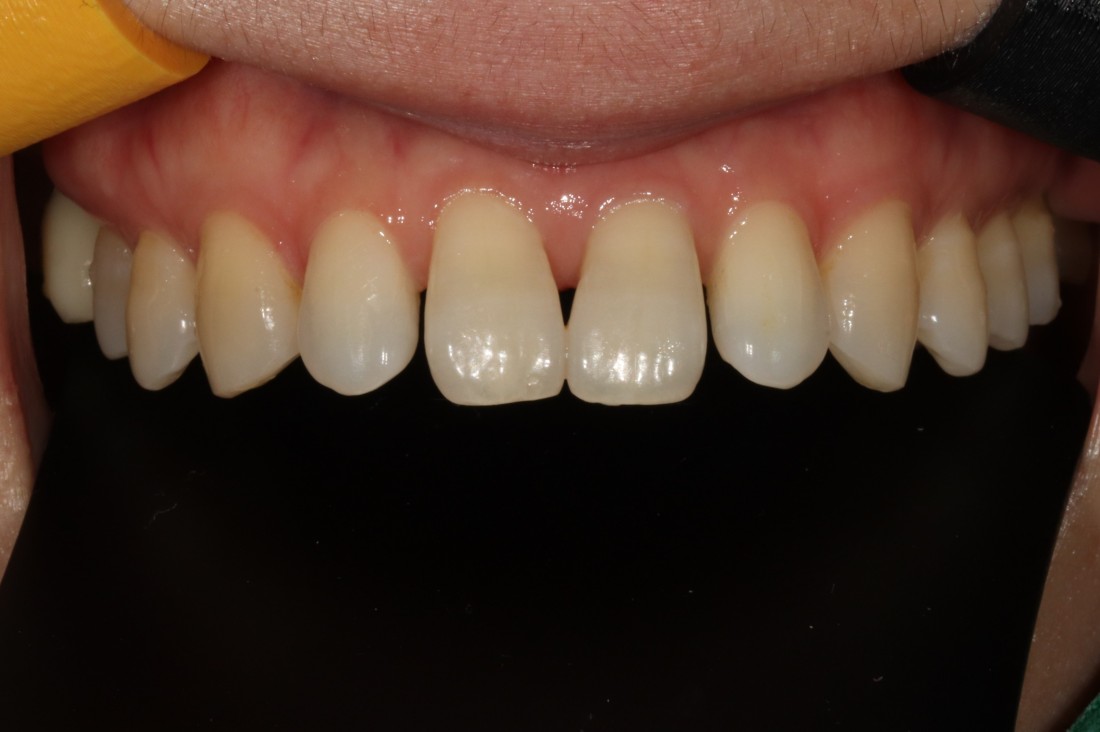

가장 환하게 웃을 때 보이는 치아가

윗니 6개 (육전치) 이기 때문에

라미네이트 상담 시

가장 많이 추천해드리고 있는데요.

전체 치아교정을 하기에는

시간, 비용이 부담되시는 분들에게

벌어진 치아의 경우

무삭제(최소삭제) 라미네이트 진료를 통해

일주일만에 빠르게 급속치아교정 효과를

얻을 수 있는 광주 라미네이트 진료를

추천드립니다.